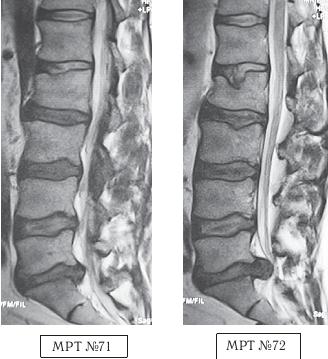

МРТ № 4

МРТ № 5

На МРТ № 4 наблюдается межпозвонковый диск в начальной стадии развития дегенеративно-дистрофического процесса.

На МРТ № 5 наблюдается межпозвонковый диск на более поздней стадии развития дегенеративно-дистрофического процесса.